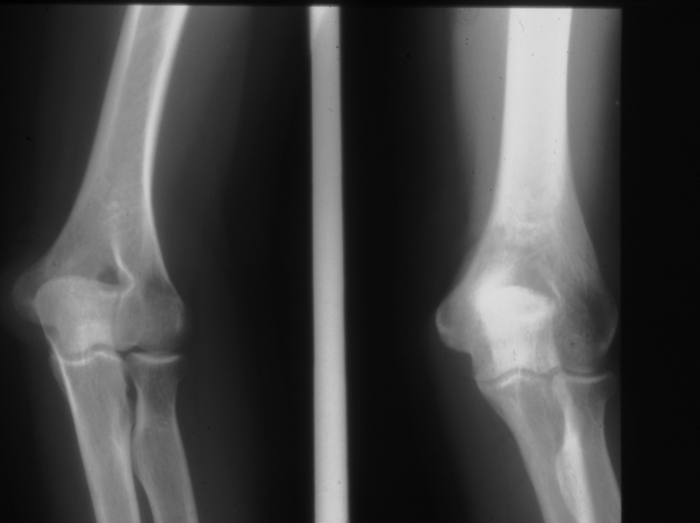

Radiology MS 28 - Normal Elbow

Identify: humerus, radius, ulna, capitulum, radial head, olecranon